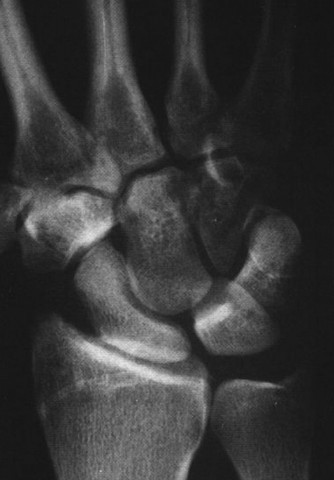

Radiographic evaluation requires specific, non-standard views. A standard PA and lateral of the wrist will often obscure the pisiform due to bony overlap. Therefore, a 30-degree supinated lateral view or a carpal tunnel view is essential to profile the pisiform and evaluate the pisotriquetral joint space. In cases of delayed union or subtle comminution, a fine-cut non-contrast Computed Tomography (CT) scan provides invaluable three-dimensional mapping. For the elderly patient presenting with progressive, non-traumatic base of thumb pain, standard radiographs must include a Robert's view (a true AP of the first CMC joint) and stress views to evaluate the degree of radial subluxation. The image above clearly demonstrates advanced 1st CMC arthritis, characterized by complete loss of joint space, subchondral sclerosis, and osteophyte formation, confirming the diagnosis.